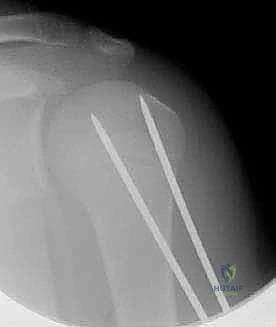

الرد المغلق والتثبيت بأسلاك كيرشنر عبر الجلد (CRPP):

هذه التقنية هي المفضلة في الكثير من كسور عظم العضد القريب. يتم إرجاع العظم إلى مكانه الصحيح تحت جهاز الأشعة السينية المتحرك (C-arm) في غرفة العمليات دون فتح الجلد. ثم يتم إدخال أسلاك معدنية رفيعة جداً (K-wires) عبر الجلد لتثبيت الكسر. تُترك نهايات الأسلاك خارج الجلد ليتم سحبها بسهولة في العيادة بعد 3-4 أسابيع دون الحاجة لعملية أخرى. -